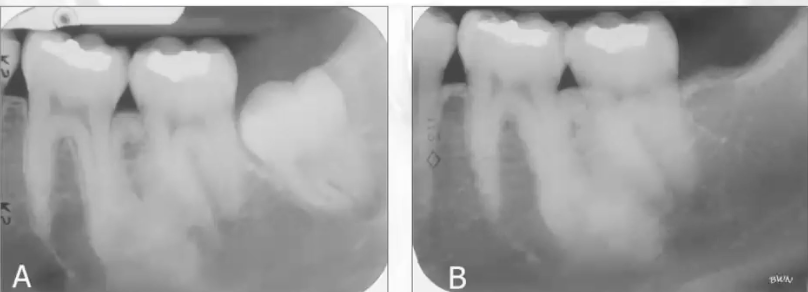

What is this image showing?

Huge expansion and swelling in left mandible area seen in chondrosarcoma

What is this radiograph showing

Mixed radiolucent and radiopaque lesion seen in chondrosarcoma; lacks a well-defined border